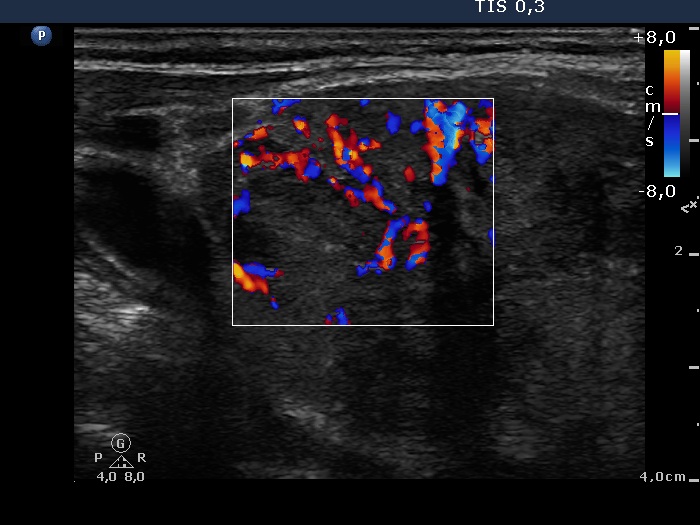

Left lobe, longitudinal view, color Doppler mode. This is an irregularly increased intranodular vascular pattern.